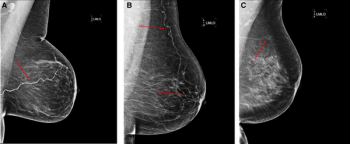

When there are equivocal findings with digital breast tomosynthesis (DBT), spot compression views may significantly enhance specificity and accuracy, and could reduce additional workup in benign cases.